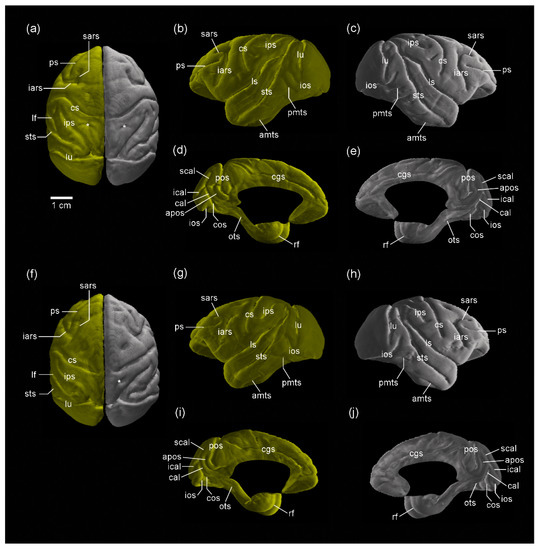

3.1. MR Images and 3D-Rendered Images

3.2. MRI-Based Morphometry